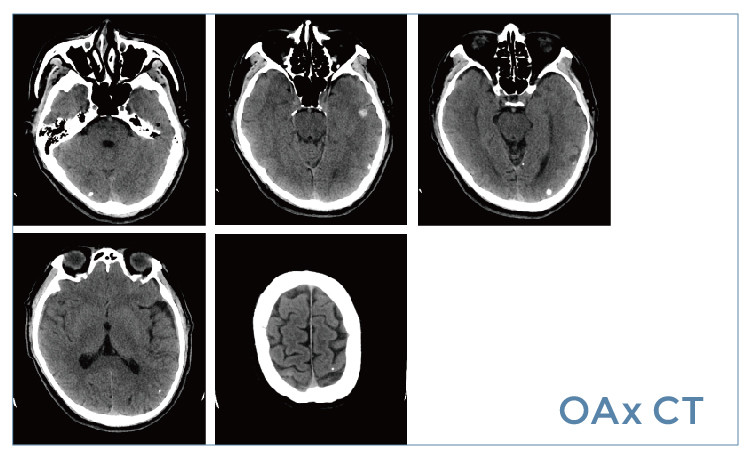

【朗润影像档案】磁共振影像病例分享(编号20190524)